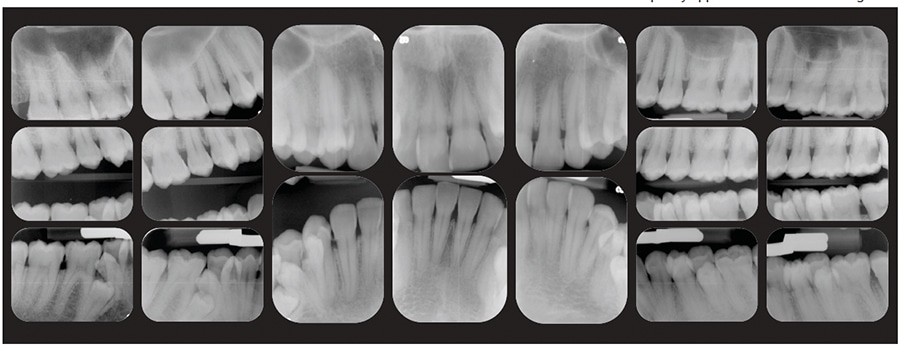

The periodontal classification was determined to be gradual-onset, generalized slight chronic periodontitis, modified by dentition (tooth anatomic factors). Clinical examination revealed no restorations and a large caries lesion on the distal of the upper left second molar, and incipient lesions on the occlusal surfaces of lower-left first and second molars, and lower-right second molar. Panoramic and full-mouth radiographic surveys revealed a lower-left impacted distomolar and lower-right supplemental premolar, and lower-right distomolar (Figure 2 and Figure 3), bringing the number of supernumerary teeth to 10. The patient was noted to have minimal supragingival calculus and generalized heavy subgingival calculus. The visual exam and a disclosing solution revealed only minimal plaque/biofilm accumulation.